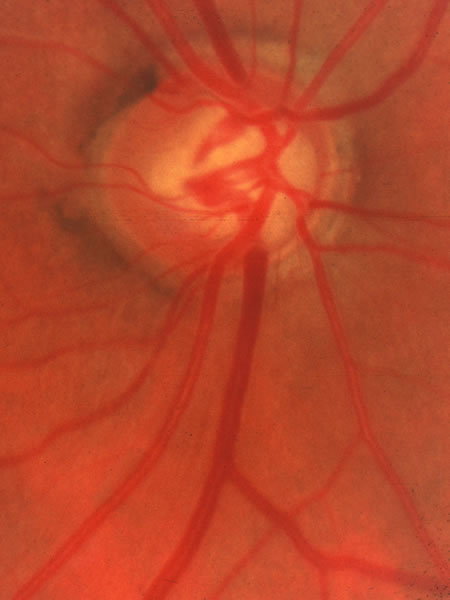

In the retinal nerve fiber layer, axons converge from every direction toward the optic disc and turn to enter the optic nerve through an opening in the outer retina, the choroid, and the sclera. The features and anatomic variation of the normal optic nerve head, or optic disc, are illustrated in Figures 2, 3, 4, 5, 6, 7, 8, 9, 10, 11, 12, 13, 14, 15, and 16. A physiologic excavation (cup) results if the chorioscleral canal is larger than required for the approximately 1 to 1.5 million axons and the supporting glial cells and blood vessels. The size of the excavation depends on how ample is the size of the chorioscleral canal.20,21 In discs where the chorioscleral canal matches the number of axons, the chorioscleral canal itself is typically somewhat taller than it is wide (Figs. 2 and 3). However, because the number of nerve fibers entering the upper and lower poles of the disc is greater than in the temporal and nasal sectors, the boundary of the physiologic cup is more or less circular.22 When the disc is large, it may be nearly circular but the cup likewise nearly circular. However, except in discs of anomalous shape, the width of the rim of neuroretinal tissue is noted in normal, nonglaucomatous optic discs to be greatest in the inferior meridian followed by the superior meridian, and narrowest in the temporal quadrant.23

Fig. 2. Normal optic nerve configuration. Notice that the height (H) of the disc is greater than the width (W). The width of the neuroretinal tissue (A) is also greater in the vertical meridian than in the nasal and temporal meridians (B); thus, the physiologic cup is round.

Fig. 3. Normal disc untilted, taller than it is wide. The neuroretinal tissue in the upper and lower sectors is more abundant in these sectors than others, so the central cup is round. A narrow white line marks the disc boundary and represents the lip of sclera that in humans almost universally separates the choroid from the optic disc tissue around the entire circumference.